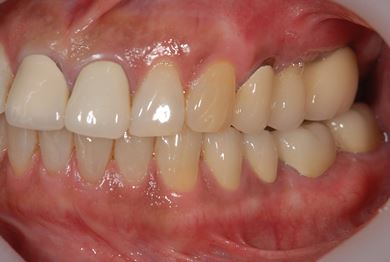

骨再生インプラント治療+セラミック治療+歯肉歯槽骨整形手術

| 性別/年齢 | 女性 / 57歳 | ||||||||||||||||||||||||||||||||

| 主訴 | 左奥上の歯ぐきの痛みの治療相談。 | ||||||||||||||||||||||||||||||||

| 治療内容 | インプラント2本(ソケットリフト、GBR)、メタルボンドセラミッククラウン3本、歯肉歯槽骨整形手術 | ||||||||||||||||||||||||||||||||